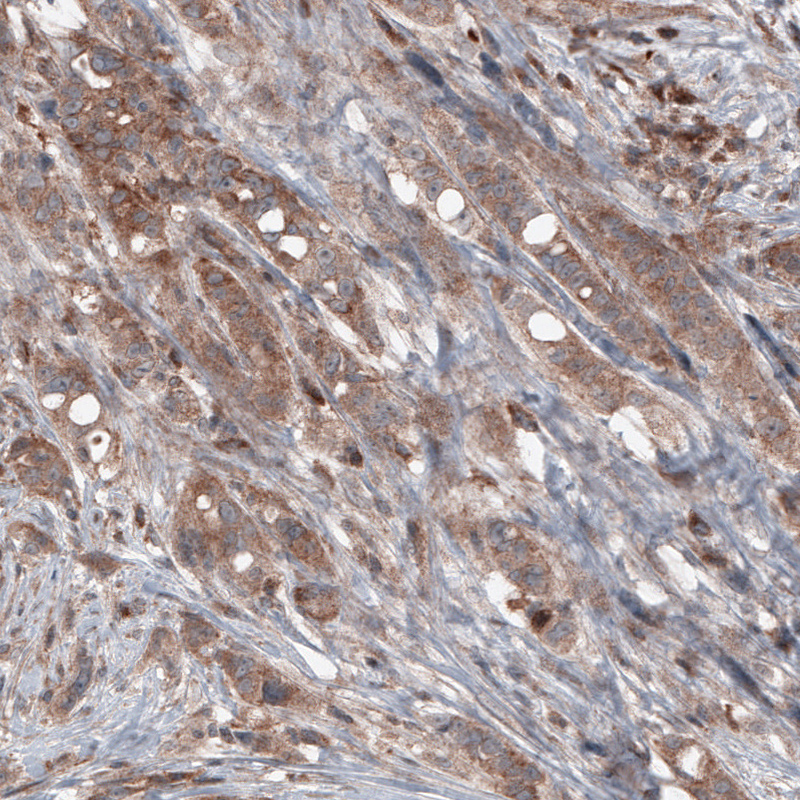

Immunohistochemical staining of human prostate cancer shows moderate cytoplasmic immunoreactivity in tumor cells.